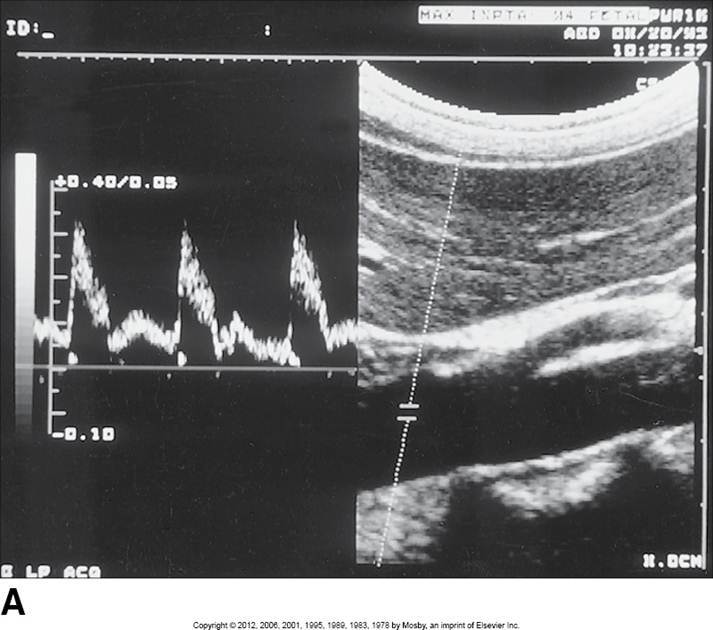

Proximal aorta

High systolic peak

Low diastolic comp.

Clean window